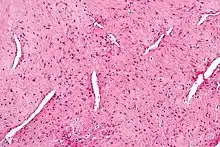

Micrograph of a nasopharyngeal angiofibroma H&E stain.